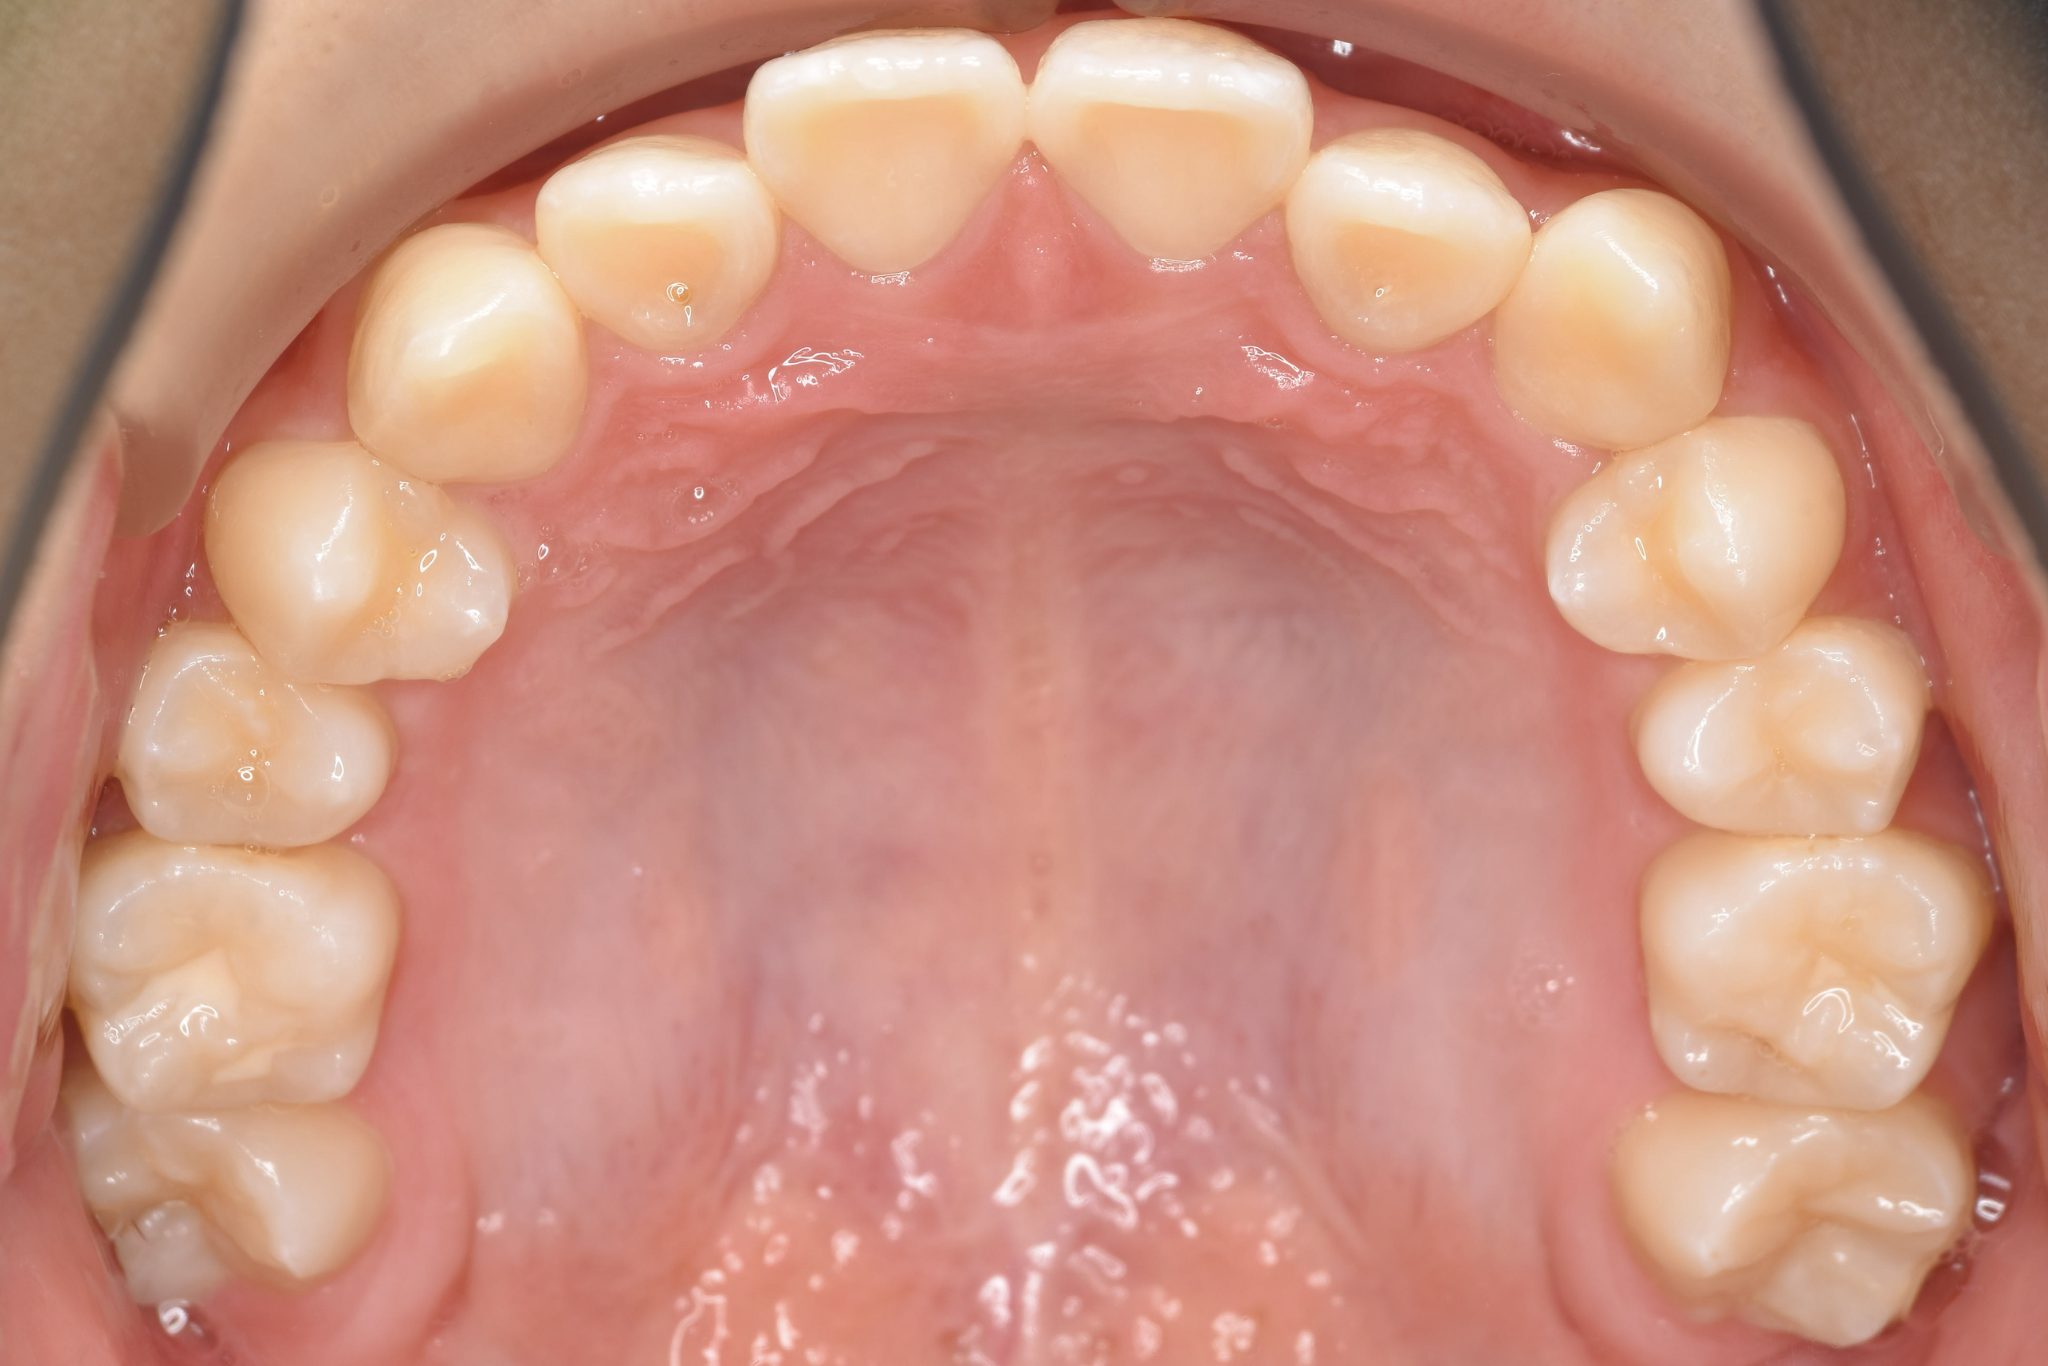

全顎ワイヤー矯正 症例_185

アフター

主訴 歯並び|横から生えている大人の歯

施術内容 小児矯正1期治療

治癒期間 4年間

費用 522,960円(税込)